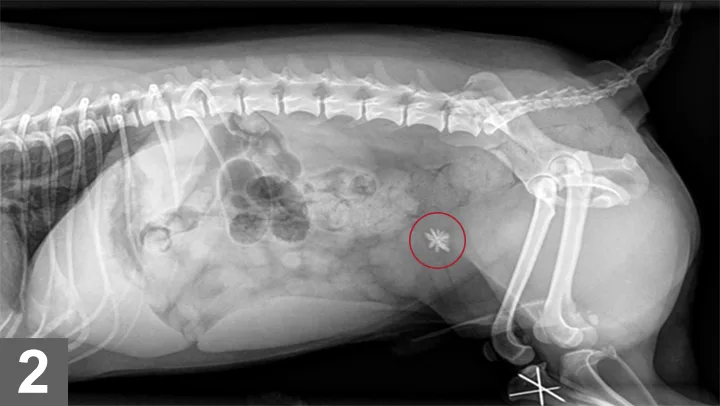

Silica-containing uroliths were rst reported in the United States in 1976 as associated with an increased use of plant-derived ingredients by the pet food industry and an increased availability of crystallographic techniques for urolith analysis. Silica-containing uroliths frequently, but not always, have a jack shape (Figure 1), although not all jack-shaped stones are silicates (ammonium urate, calcium oxalate, and struvite uroliths may also be jack-shaped). Silica-containing uroliths occur infrequently in dogs. Incidence ranged from 0.4%9.6%1-6 in several large retrospective studies at urolith analysis laboratories. Many of the reported silica-containing uroliths in the United States have occurred in German shepherd dogs, shih tzus, old English sheepdogs, and golden and Labrador retrievers. Most silica-containing uroliths are diagnosed in dogs 68 years of age, and males are affected more commonly than females (>9:1 M:F).2 In most dogs, numerous silica uroliths form, versus a solitary urolith. Silica-containing uroliths are radiographically opaque compared with surrounding soft tissue (Figure 2).

Figure 2

Lateral radiograph of a dog with a solitary silicate urolith.

Additional preventive measures after surgical management include increasing urine volume and eradicating any UTIs. Lowering the urine specic gravity decreases the urinary concentration of silica. Feeding canned food helps increase water intake as will making available multiple sources of clean, fresh water. Maintenance of a urine specic gravity of less than 1.020 is ideal, and dogs should be allowed frequent opportunities to void. Urine sediment and pH should be monitored routinely, and UTIs should be treated promptly based on bacterial culture and sensitivity results. Lateral abdominal radiographs should be taken periodically, and if there are signs of a lower urinary tract inflammation, abdominal radiographs (Figure 2) help rule out urolith recurrence. Because soil contains high concentrations of silica, consumption of dirt and grass should be discouraged.